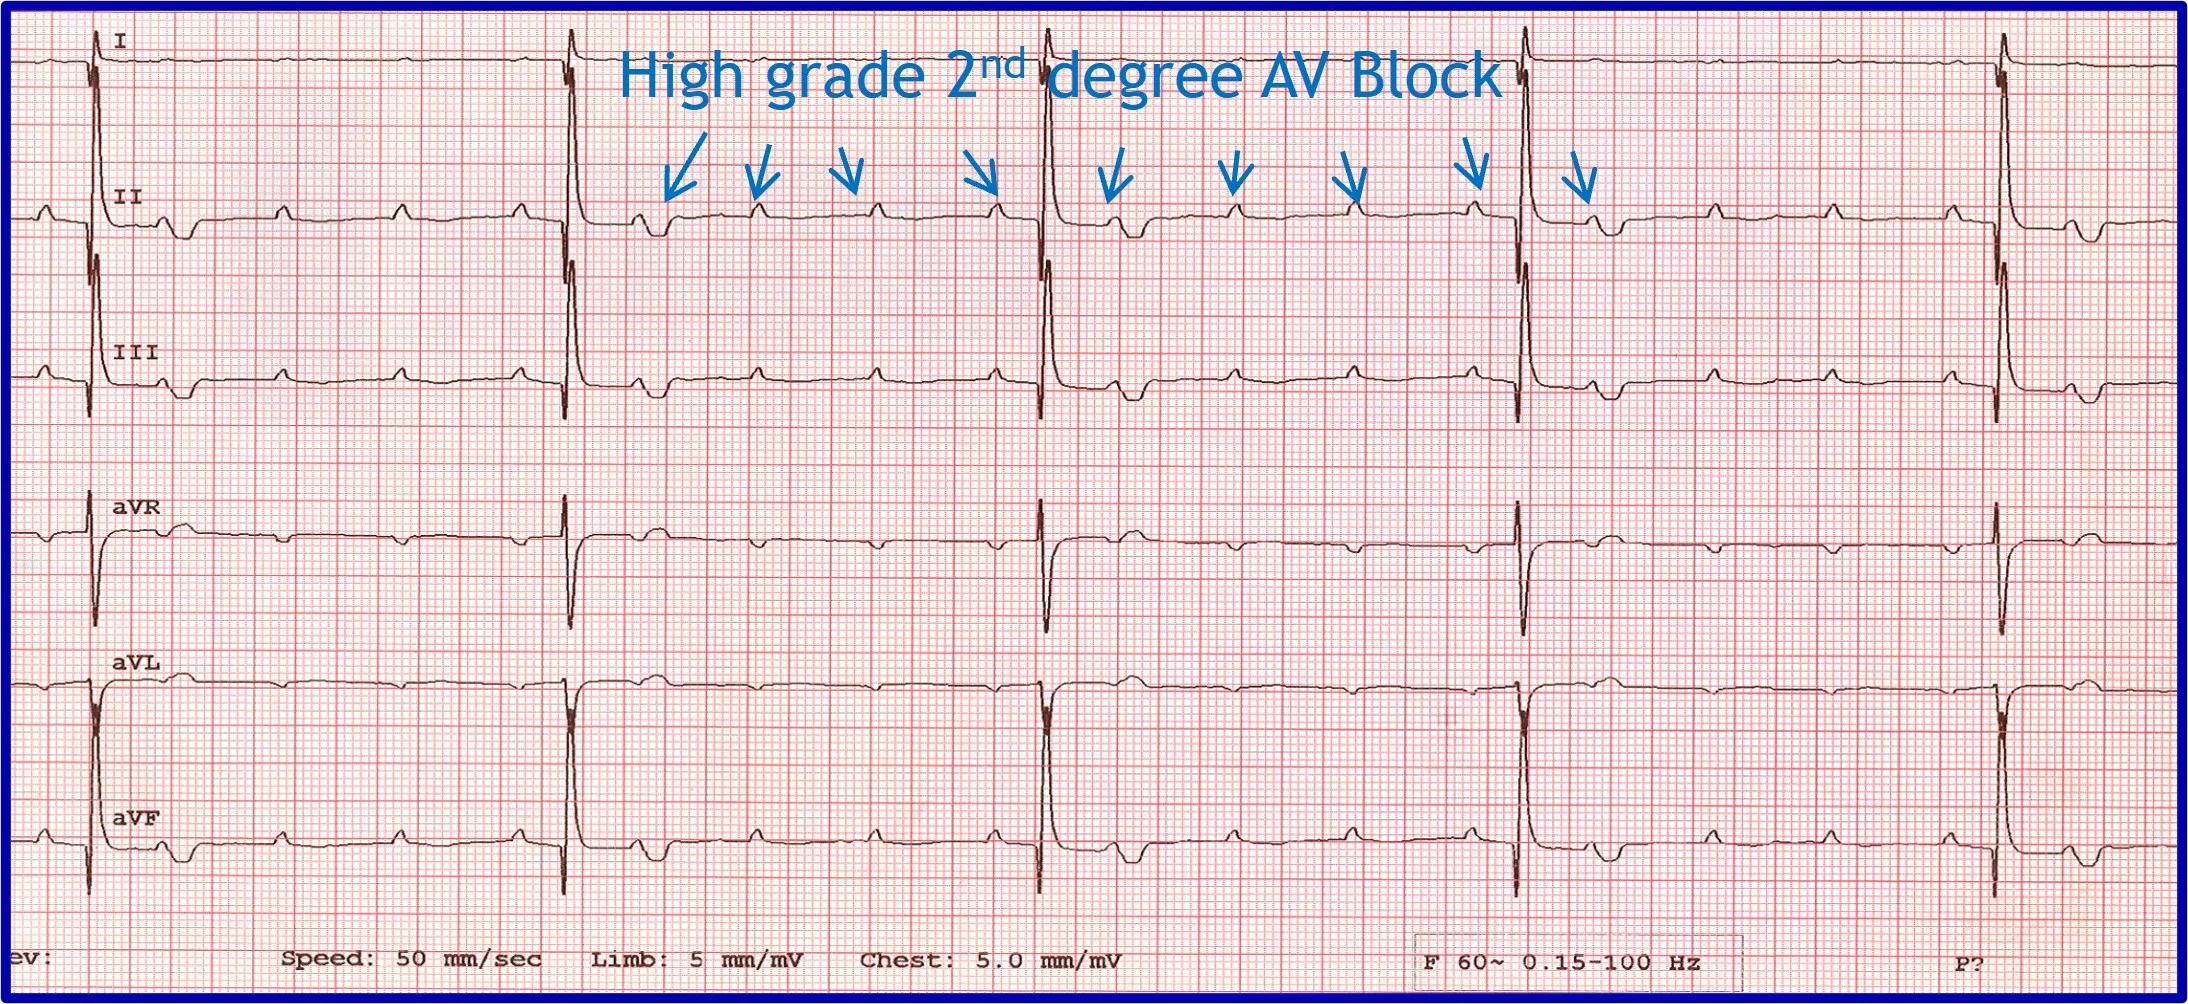

Evaluation of an arrhythmia with AV nodal disease includes determination of whether the arrhythmia is hemodynamically important (ie, rhythm is slow enough to cause clinical signs, including exercise intolerance, syncope, and signs of congestive heart failure) and whether there is autonomic influence on the arrhythmia that can be accomplished with administration of a high-end dose of atropine (0.04 mg/kg SC or IM). Expected response for a normal sinus or AV node with excessive vagal influence is complete resolution of the AV block and a heart rate >160 to 180 bpm (Figure 5).

(A) ECG in a patient with high-grade second-degree AV block in which no 2 consecutive P waves are conducted to create ventricular depolarization. Each QRS complex has a P wave with a constant PR interval, but many P waves do not have an accompanying QRS complex. (B) Thirty minutes after administration of atropine (0.04 mg/kg IM), ECG showed complete resolution of the AV block, 1:1 conduction of every P wave, and heart rate >180 bpm, indicating the SA and AV nodes are fully functional and the prior delay in conduction was vagally mediated.